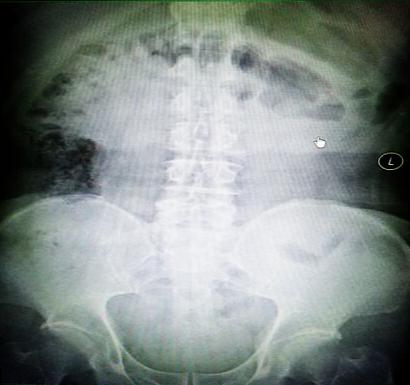

受試患者在結腸端端吻合術中,使用我司新研制產品達到了理想的預期效果?;颊咝g后7天、14天X光片顯影,可降解腸道支架均能按研制設計的預期時間節點保持應有強度,術后21天X光片顯示可降解腸道支架已完全破碎,并排出體外。在整個試驗過程中,病患無任何不良反映,耐受良好。